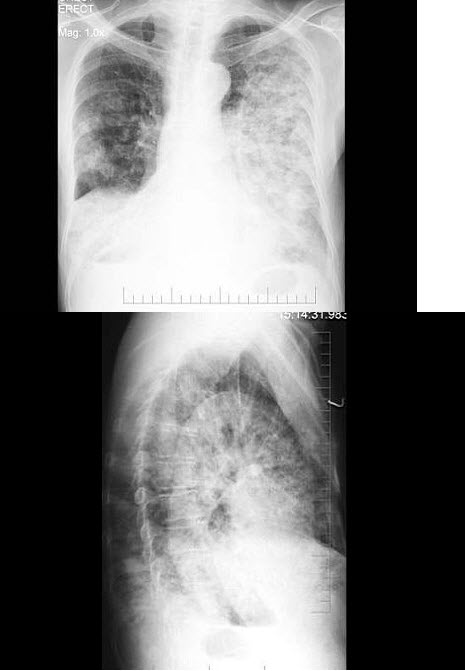

13、单项选择题

男,52岁,从事矿井工作32年,近几年出现气喘,呼吸困难,胸片如图,其最可能的诊断为()